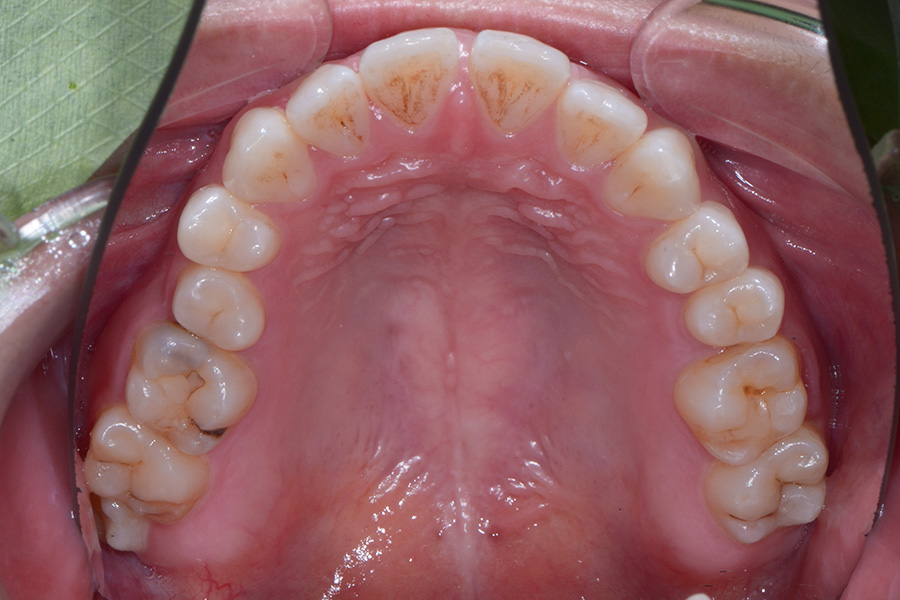

• 治療後